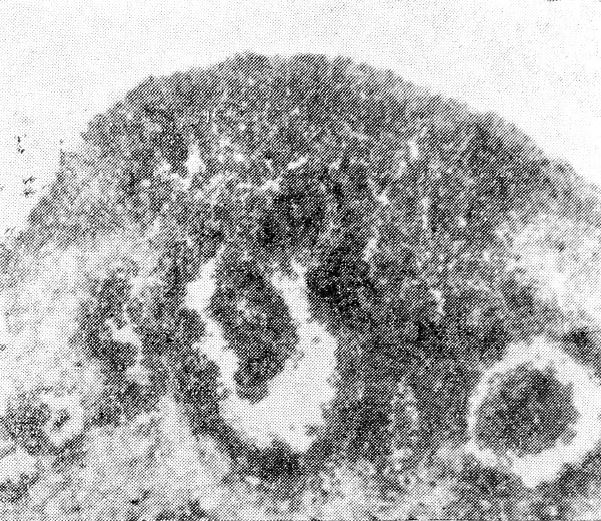

С целью более подробного изучения этого явления нами дополнительно исследовано 20 случаев. Вскрытие трупов производилось через 12—26 часов после смерти. При микроскопическом исследовании мозга мы наблюдали во всех случаях резкое полнокровие и выраженный отек ткани мозга. При этом только в одном случае имелись кровоизлияния в подкорковом узле, в двух случаях — в мозжечке и во всех 20 случаях — в продолговатом мозге. При исследовании поперечных срезов продолговатого мозга почти под эпендимой дна 4-го желудочка, главным образом в верхней половине ромбовидной ямки, во всех случаях (100%) мы обнаружили кровоизлияния, причем иногда довольно обширные (рис. 1 и 2). Нарушения целости кровеносных сосудов мы не наблюдали. По-видимому, выхождение крови из кровеносных сосудов происходило путем диапедеза. Закономерность описанных наблюдений находит свое анатомическое обоснование в работах В. Г. Петровой-Мурафа, показавшей своеобразный зональный характер кровоснабжения продолговатого мозга и всей ЦНС в целом. Одновременно мы, как и другие исследователи (T. С. Матвеева), наблюдали выраженные дистрофические изменения нервных клеток (отек, вакуолизация, распад ядер, слабое восприятие окраски и проч.).

Рис. 1. Увеличено в 300 раз. Окраска гематоксилин-эозином

Рис. 2. Увеличено в 180 раз. Окраска гематоксилин-эозином